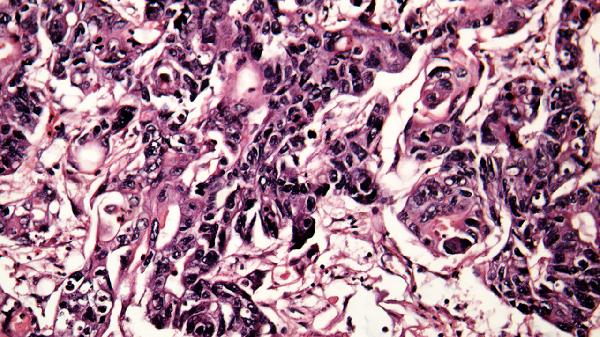

雙肺磨玻璃影可能是由肺炎、肺水腫、間質(zhì)性肺病、肺出血或早期肺癌等疾病引起的,是否嚴(yán)重需結(jié)合具體病因判斷。雙肺磨玻璃影的嚴(yán)重程度與病因相關(guān),部分情況可能為暫時性病變,部分可能提示嚴(yán)重疾病。

肺炎引起的雙肺磨玻璃影通常由細(xì)菌、病毒或真菌感染導(dǎo)致,患者可能出現(xiàn)咳嗽、發(fā)熱、呼吸困難等癥狀。治療需根據(jù)病原體選擇抗生素、抗病毒藥物或抗真菌藥物,如阿莫西林克拉維酸鉀片、磷酸奧司他韋膠囊等。肺水腫多與心力衰竭或液體負(fù)荷過重有關(guān),表現(xiàn)為氣促、端坐呼吸,需利尿劑和原發(fā)病治療。間質(zhì)性肺病屬于慢性進(jìn)展性疾病,可能與環(huán)境暴露或自身免疫病相關(guān),需糖皮質(zhì)激素或免疫抑制劑干預(yù)。肺出血常見于血管炎或凝血障礙,需止血和病因治療。早期肺癌若表現(xiàn)為磨玻璃影,需通過病理活檢明確性質(zhì),部分可手術(shù)切除。

雙肺磨玻璃影若為感染性或暫時性病變,經(jīng)規(guī)范治療多可好轉(zhuǎn);若為間質(zhì)性肺病或惡性腫瘤,則需長期管理。建議發(fā)現(xiàn)影像學(xué)異常時完善血?dú)夥治?、病原學(xué)檢查、腫瘤標(biāo)志物等進(jìn)一步評估,避免吸煙及接觸粉塵等危險因素,定期隨訪胸部CT觀察病變動態(tài)變化。